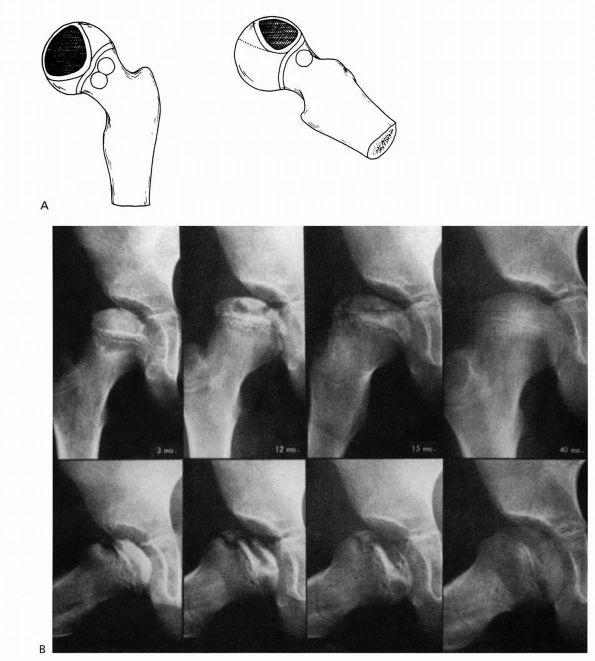

FIGURE 15-17. (A)

Catterall group 2 disease: anterolateral involvement, sequestrum formation, and a clear junction between the involved and uninvolved areas. There are anterolateral metaphyseal lesions, and the subchondral fracture line is in the anterior half of the head. The lateral column is intact. (B) Catterall group 2 disease 3 to 40 months after onset of symptoms. Note the intact lateral pillar. (Weinstein SL. Legg-Calvé-Perthes disease. In: Morrissy RT, Weinstein SL, eds. Lovell and Winter’s Pediatric Orthopaedics, 5th Ed. Philadelphia: Lippincott Williams and Wilkins, 2001:975) |

favorable prognosis than whole femoral head involvement. Catterall

demonstrated the importance of the extent of epiphyseal involvement

relating to prognosis and proposed four groups based on the presence or

absence of seven radiographic signs in 97 untreated hips (Table 15-1; see Figures 15-16 and 15-19).

He reported that 90% of the good results in untreated patients were in